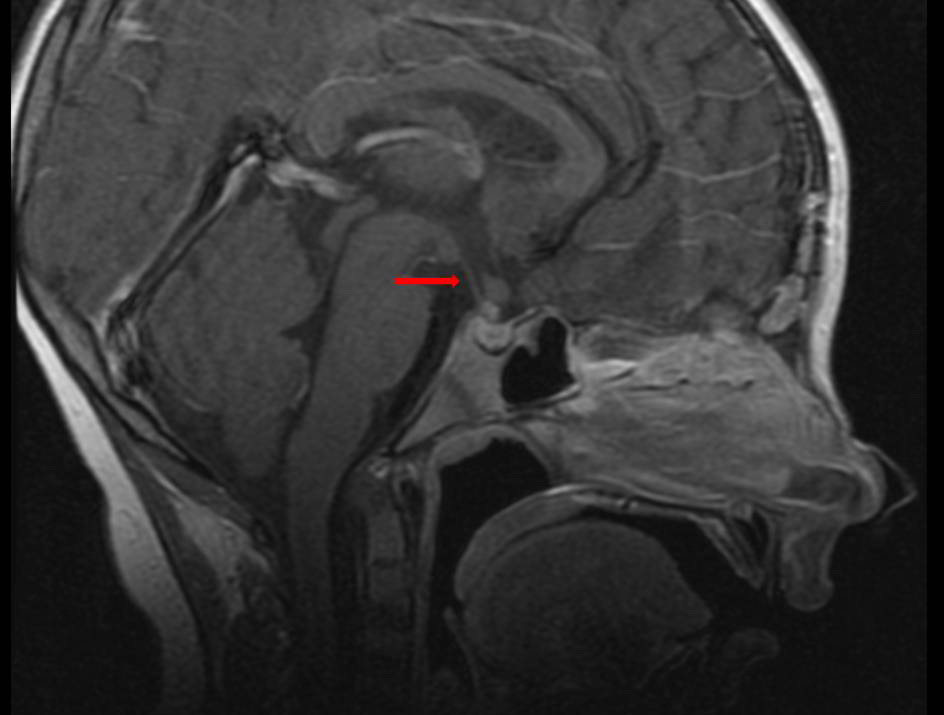

Tras recibir tres ciclos de quimioterapia, se realiza una resonancia magnética de control en la que se visualiza una disminución del grosor del tallo hipofisario de 10 mm a 3 mm. La paciente está pendiente de recibir a continuación 25 sesiones de radioterapia.